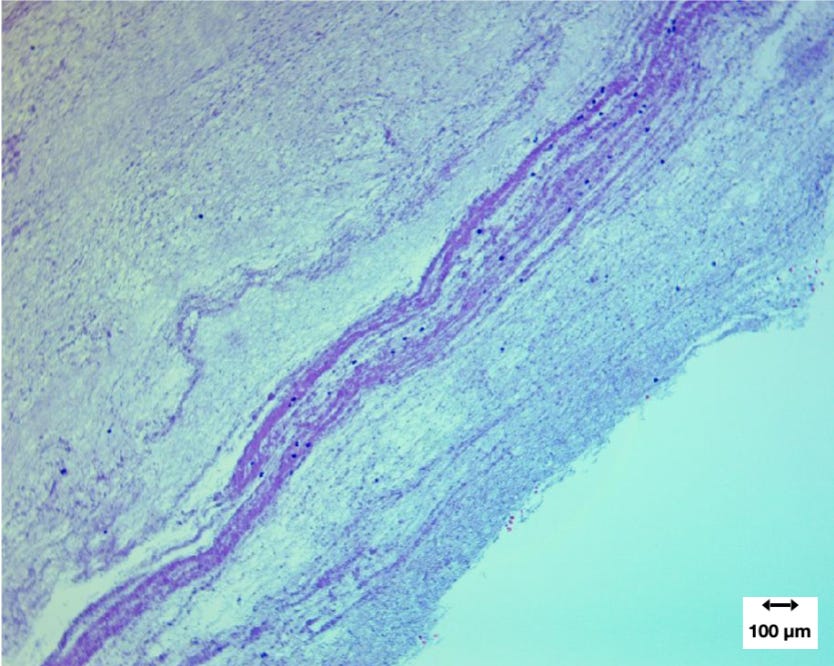

Microscopic analysis provided further insight into the internal architecture of the casts. Samples preserved in formalin were embedded in paraffin, sectioned into thin slices, and stained for microscopic examination.

A composite set of micrographs revealed heterogeneous internal architecture, including regions of dense fibrin fibers and scattered cellular material.

At low magnification, researchers observed irregular fibrous matrices with large void spaces. These voids are common artifacts produced during tissue processing when unsupported regions collapse or detach.

At intermediate magnification, clusters of cellular nuclei appeared scattered throughout the fibrin network. However, the overall cellular density was low compared with typical thrombi.

One of the most important findings was the presence of Lines of Zahn, layered structures that form when blood clots develop in flowing circulation. These alternating bands of fibrin and cellular material are considered a hallmark of antemortem clot formation.

Although these laminations were not present throughout the entire structure, their presence indicates that at least part of the material formed while blood was actively circulating. This means that these “calamari clots” can and do form while C-19 injected individuals are still alive, not just after their death as some have proposed.